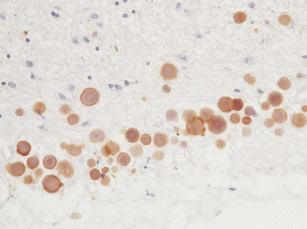

|   | 14/11/2016 | Los cuerpos amiláceos cerebrales se tiñen con anticuerpos frente a hongos en distintas enfermedades neurodegenerativas | Ver detalles |